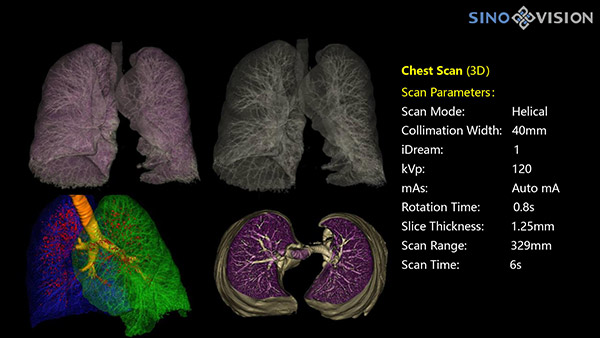

Инновационный 128-срезовый компьютерный томограф SinoVision InsitumCT 568 – это сочетание высокой скорости работы, низкой дозы и максимума возможностей для подавляющего большинства клинических случаев, как в рутинных, так и в углубленных специализированных исследованиях, в том числе педиатрические и кардиологические исследования при сверхнизких дозах.

РМК

Полнофункциональный 128-резовый компьютерный томограф InsitumCT 568 - это лучшее в новом поколении широкодиапазонных томографов с 128 срезами и большой диафрагмой. Этот КТ-сканер с большой апертурой обеспечивает 128 срезов КТ с диафрагмой 76 см, улучшает разрешение изображения до 21Lp/cm, помогает точно диагностировать и лечить заболевания, а также значительно улучшает клинические характеристики и расширяемость оборудования. Позволяет реализовать визуализацию в высоком разрешении и в малых дозах лучевой нагрузки.

Полнофункциональная платформа клинической диагностики может точно определять местонахождение и диагностировать общие повреждения качественно и количественно, а также достигать полнофункциональных клинических показателей, включая обширные кардиологические исследования со сверхнизкими дозами лучевой нагрузки.

- Динамическое сканирование